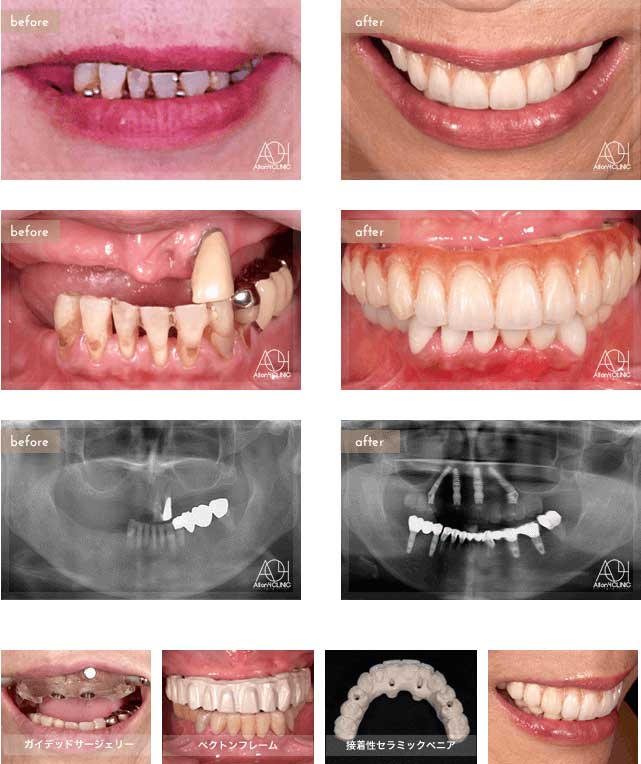

Treatment : All-on-4 zygoma

- Upper All-on-4

- Lower All-on-4

Age : 56 Sex : 男 S.T

| 主訴 | 仕事が忙しく歯には全く関心が無く、とうとう食事が困難になり治療を受ける事を決意。 |

| 治療内容 | ガイデッドサージェリーにてインプラント埋入。極めて骨量が少ないためザイゴマインプラントにて治療 |

| 治療費(総額) | ¥7,200,000(税抜)『モニター割引適用』 |

| リスク | 治療後の口腔管理が不適切な場合、埋入したインプラント周囲に感染・炎症を起こし、脱落する可能性がございます。 |